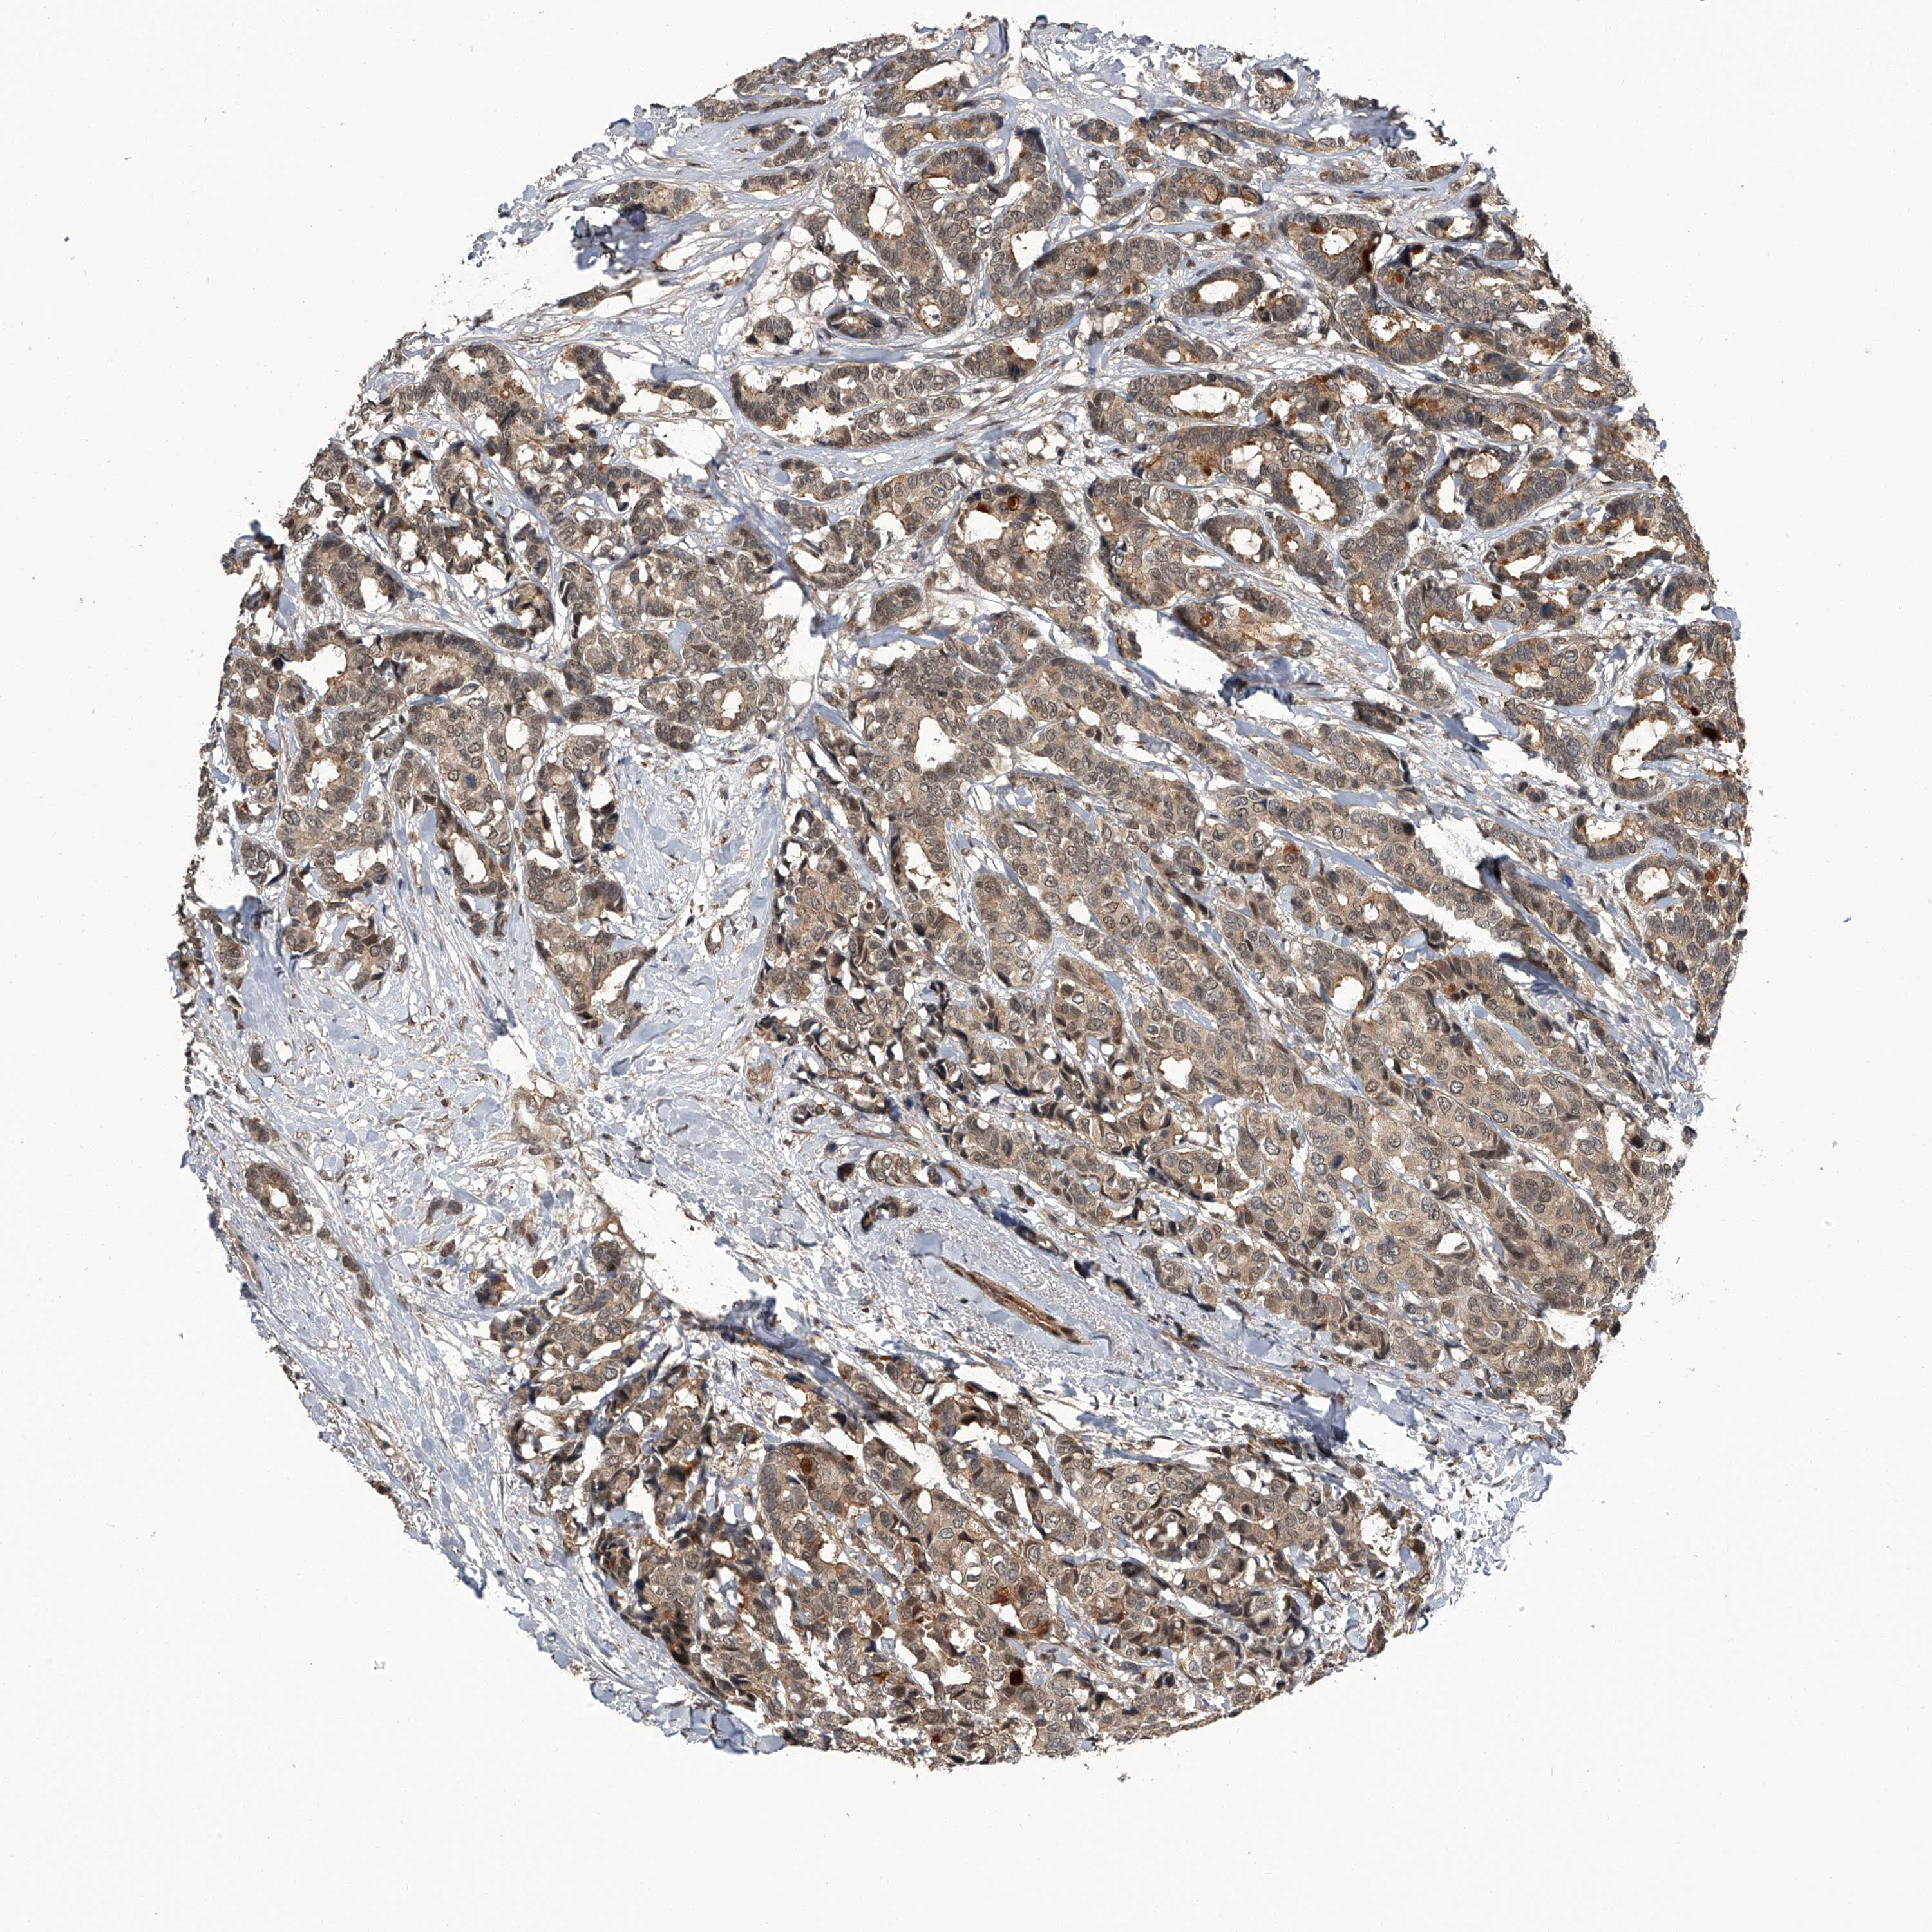

CANCER BREAST CANCER Show tissue menu

BRCA TCGA BRCA VALIDATION PROTEIN EXPRESSION